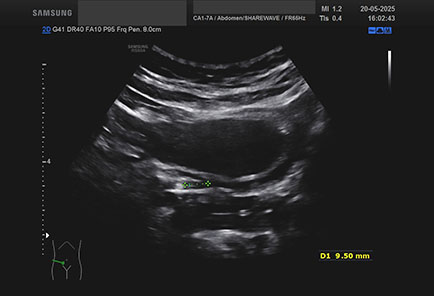

Ecografia del: 20/05/2025

Strumento: Samsung

Sonda: Convex

Età Paziente: F

Commento all'esame: giovane donna dimessa dal PS con diagnosi di cistite: calcolo ureterale in assenza di pielectasia/idronefrosi.

Conclusioni: calcolo ureterale (ureteral stone).